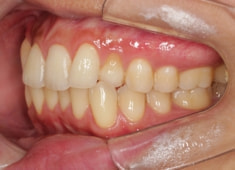

治療後(2年後)